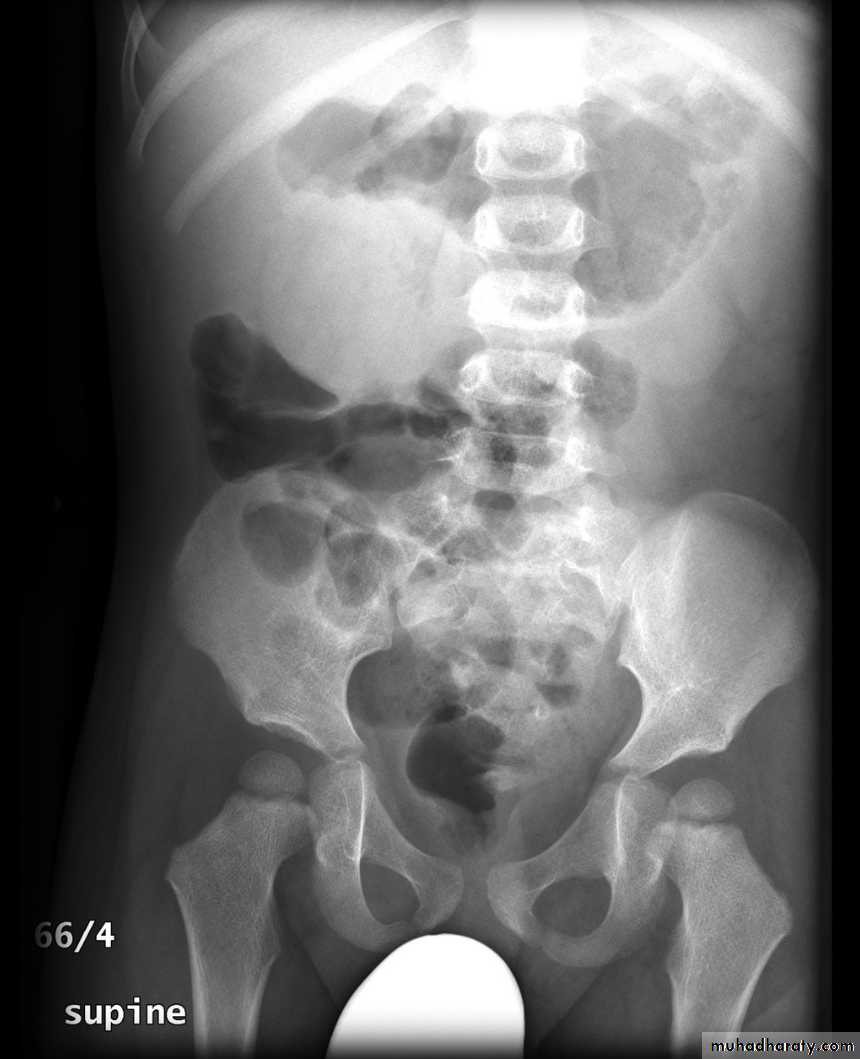

Abdominal plain film

Abdominal x-rays may demonstrate an elongated soft tissue mass (typically in the right upper quadrant in children) with a bowel obstruction proximal to it.